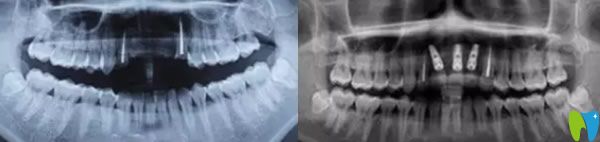

郝醫(yī)生通過醫(yī)學(xué)種植技術(shù),根據(jù)老公牙齒狀況設(shè)計種植方案。他將種植體與人體兼容性高的鈦金屬精準(zhǔn)植入缺牙區(qū)的牙槽骨內(nèi),等三個月后,人工牙和牙槽骨緊密結(jié)合,再做烤瓷牙、全瓷牙冠。郝醫(yī)生植入牙根手術(shù)完成后,老公從手術(shù)室出來牙齦看著就沒有之前那么憋了,飽滿了許多。

三個月后,我們又來到成都瑞爾口腔,醫(yī)生說恢復(fù)的很不錯,牙槽骨和種植體已經(jīng)緊密結(jié)合,可以安裝基臺,戴上牙冠后,牙齒咀嚼功能恢復(fù)了,可承受正常的咀嚼力量,美觀上幾乎和自然牙一樣。郝亦工醫(yī)生建議后期一定要保持好口腔衛(wèi)生健康,細(xì)心呵護(hù),這樣能夠保證種植牙的使用壽命。